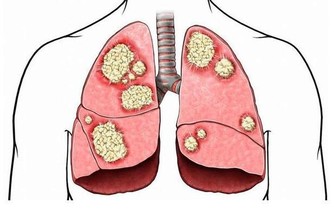

春季養生另一方面,就是要防病。

特別是初春,天氣由寒轉暖,各種致病的細菌、病毒隨之生長繁殖。

溫熱毒邪開始活動,現代醫學所說的流感、流腦、麻疹、猩紅熱、肺炎也多有發生和流行。

為避免春季疾病的發生,在預防措施中,首先要消滅傳染源;

二要常開窗,使室內空氣流通,保持空氣清新;

三要加強鍛煉,提高機體的防禦能力。

此外,注意口鼻保健,阻斷溫邪上受首先犯肺之路。